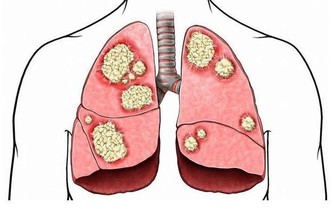

研究人員發現,晚飯喝杯紅酒,積存在人體內的致癌物質可以大量排出。

調查結果顯示,吸煙或者吃烤肉等在體內聚集的強致癌物質多環芳香烴,

在喝紅酒後會顯著降低,特別是喝了100%葡萄原汁的紅葡萄酒。

研究人員對吸煙者進行了試驗,讓他們在4天內連續每天喝200ml紅酒,

並測定喝紅酒前後尿液中多環芳香烴的代謝產物1-羥基芘含量。

結果發現,吸煙6小時後喝杯紅酒,人體血液內1-羥基芘會經尿液大量排出;如果不喝紅酒,1-羥基芘排出很少。